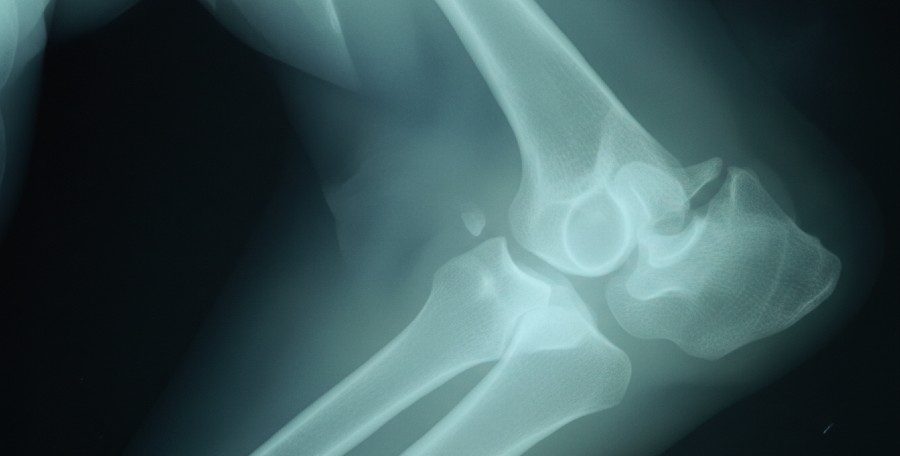

El diagnóstico de la displasia de codo debe realizarlo siempre un veterinario. Aunque los síntomas pueden orientar, no es posible confirmar este problema articular únicamente con la observación en casa. Este tipo de displasia se diagnostica principalmente mediante un estudio radiográfico completo de las extremedidas.